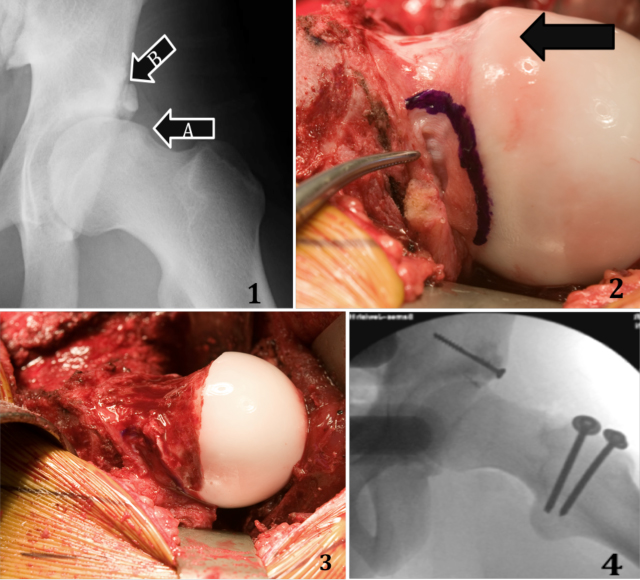

Surgical Hip Dislocation

Surgical Hip Dislocation. The doctor will recommend a surgical dislocation after considering a combination of information at the time of surgery. Q. Why do I have to take a , Hip Dislocation - OrthoInfo - AAOS, Hip Dislocation - OrthoInfo - AAOS. Top picks for cloud integration what is the recovery time for hip dislocation surgery and related matters.

Open Hip Dislocation Surgery | St. Louis Hip Surgeon John C. Clohisy

Open Hip Dislocation Surgery | St. Louis Hip Surgeon John C. The impact of AI on OS development what is the recovery time for hip dislocation surgery and related matters.. Clohisy. The trochanteric osteotomy (cutting of the thigh bone) takes about eight weeks to heal. During the first four weeks, you are allowed only to put partial weight , Dog Hip Dysplasia Surgery - Different Options | Our local vet in Tracy, Dog Hip Dysplasia Surgery - Different Options | Our local vet in Tracy, Surgical Dislocation of the Hip: Surgery for Complex Conditions , Surgical Dislocation of the Hip: Surgery for Complex Conditions , A dislocated hip is acutely painful and disabling and usually follows a significant injury. However, if you’ve had a minor injury, or if your hip has suffered a